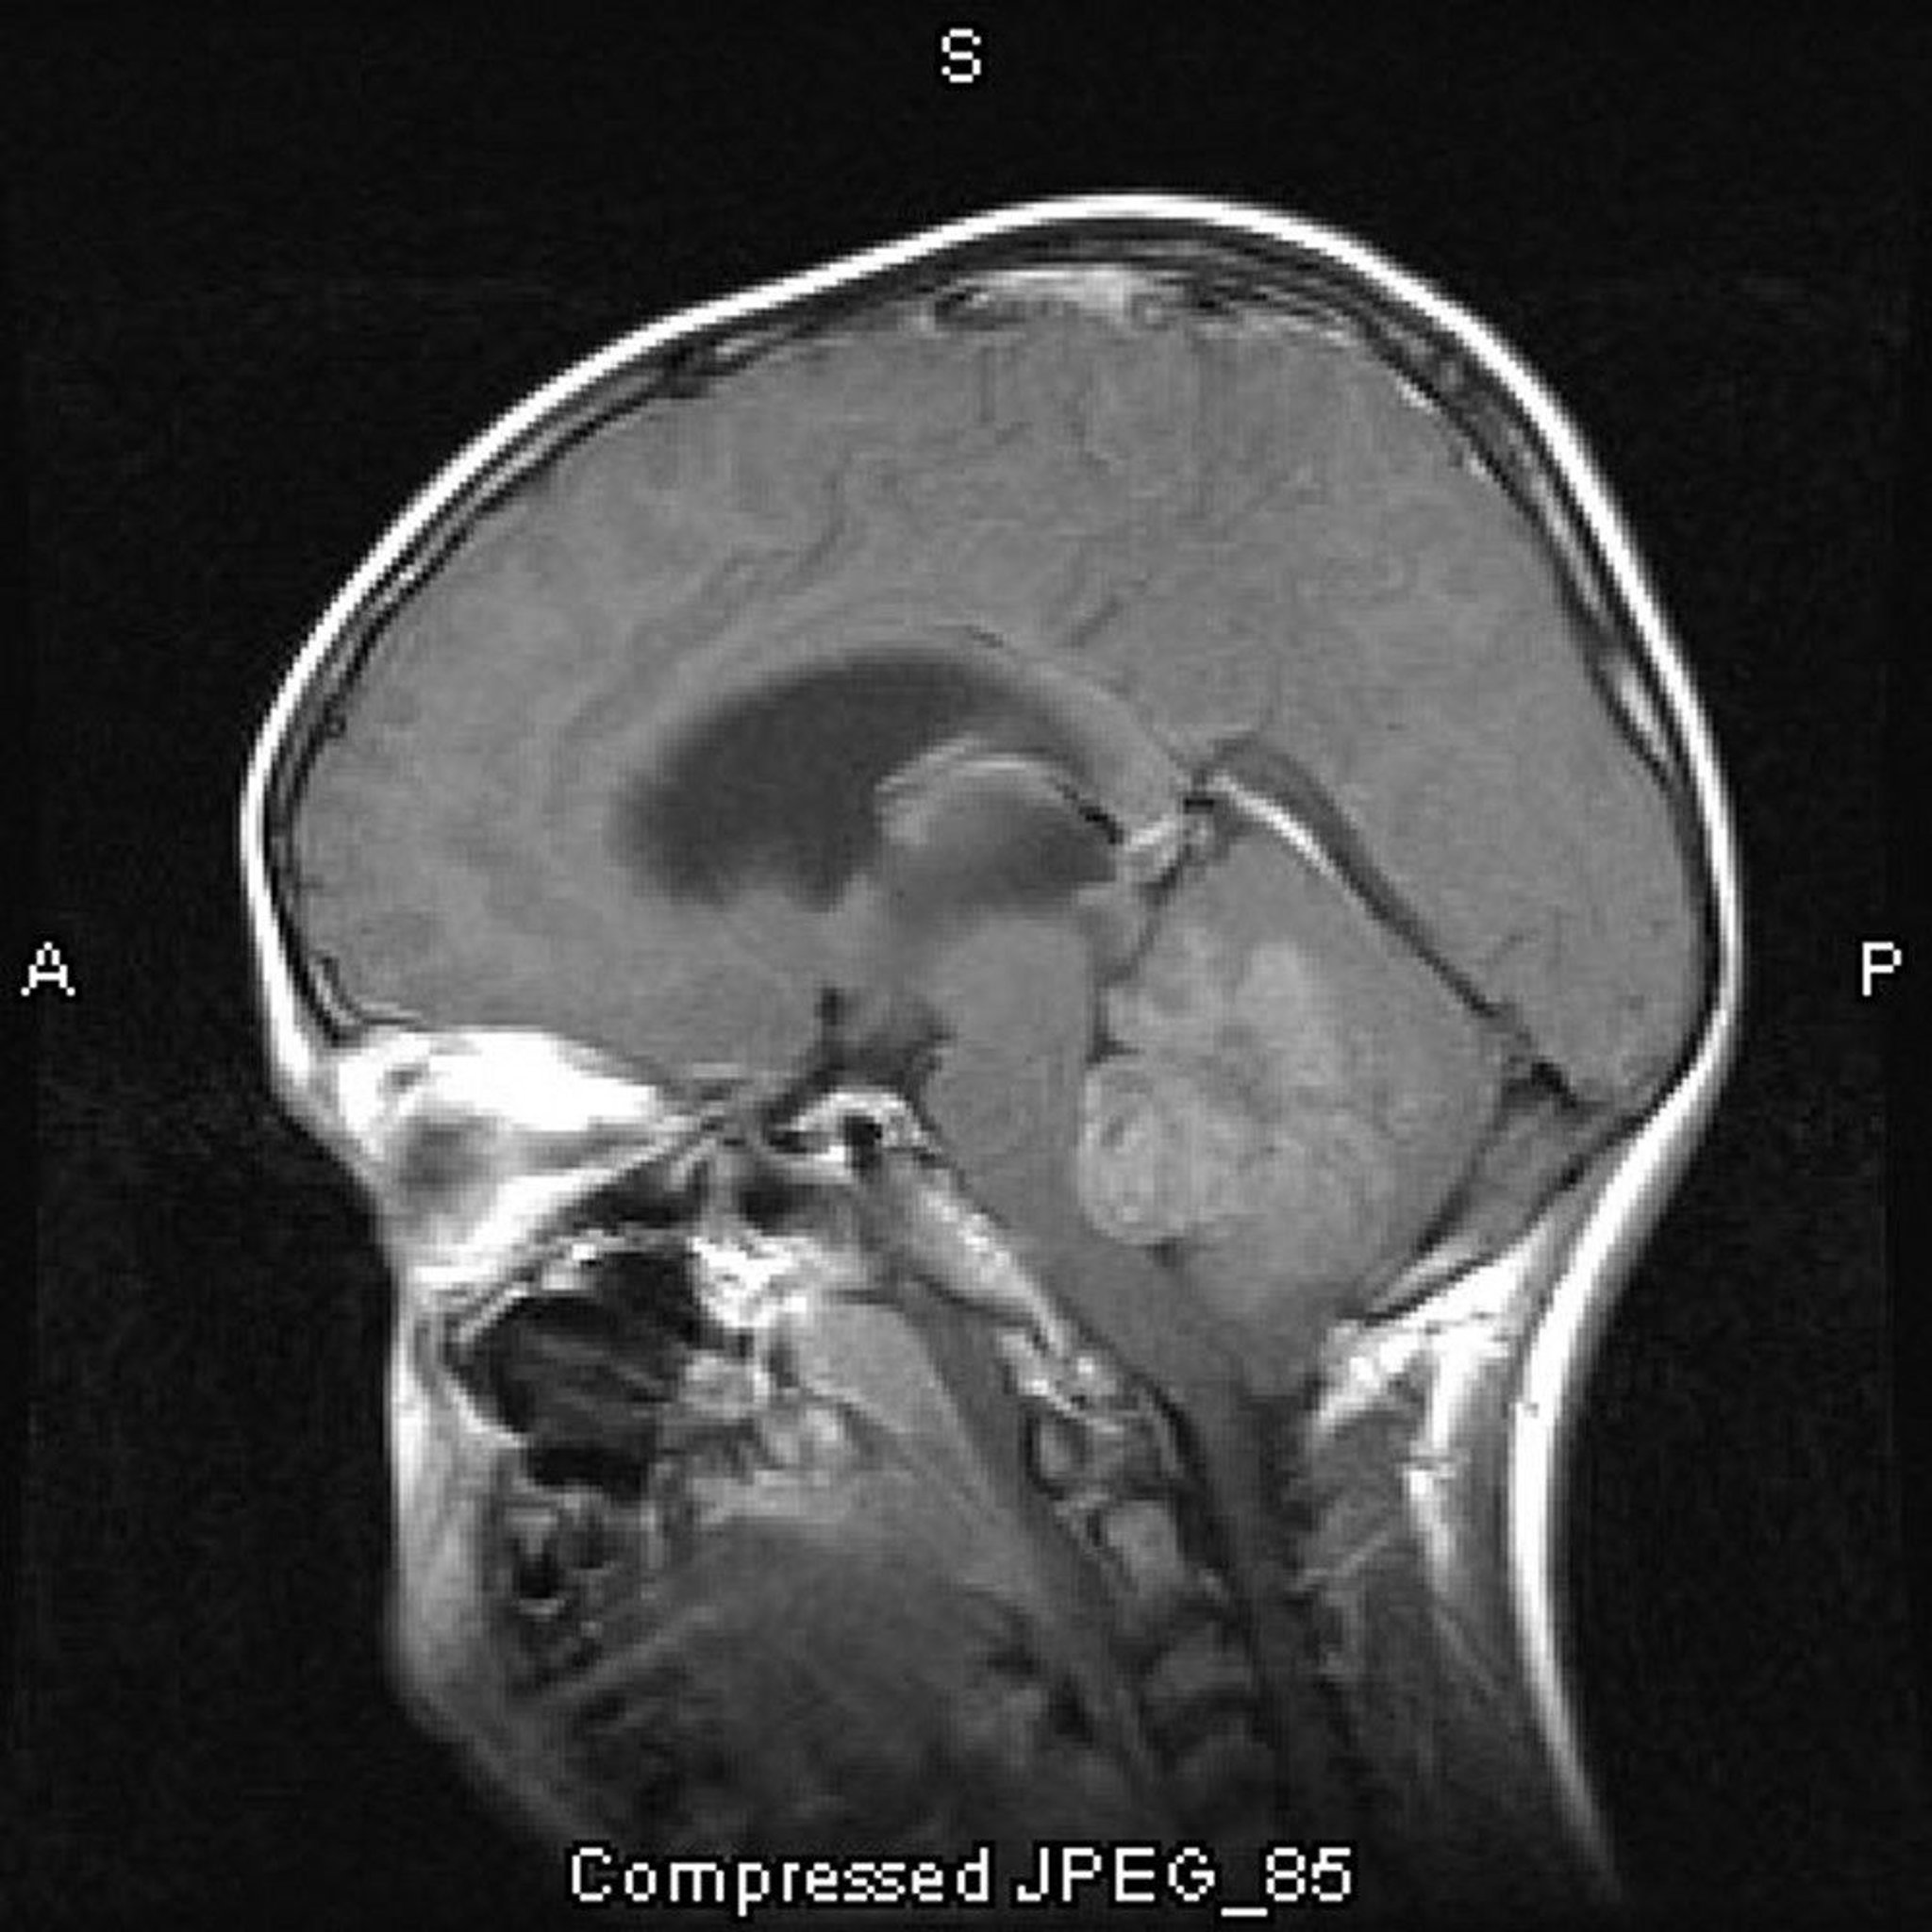

This contrast-enhanced MRI scan shows a medulloblastoma that grows in the roof of and obstructs the fourth ventricle.

Image courtesy of William R. Shapiro, MD.